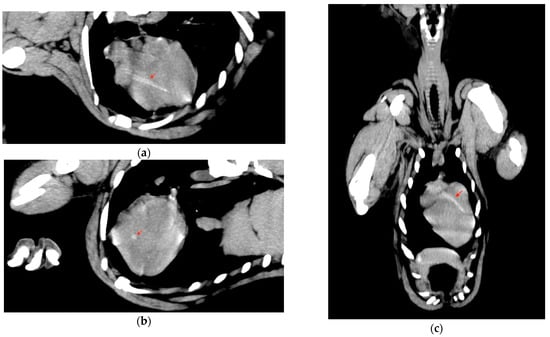

2.1. Case Description and Clinical Investigations